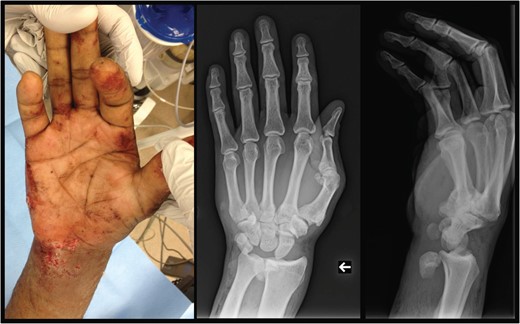

A 40-year-old male presented after a fall from two stories. Although the history and physical examination were limited secondary to intoxication and decreased Glasgow Coma Scale score, a deformity of the right wrist was observed. Physical and radiographic examination demonstrated an open, lunate enucleation with a 1.0 × 0.5 cm volar wound that communicated with bone (Fig. 1). Concern for subluxation of the second and third carpometacarpal joints (CMC) was also appreciated. However, a review of the patient's medical history demonstrated chronic CMC injuries to the right hand. Vascular examination was intact; however, a proper neurological examination was unobtainable due to the patient's obtunded condition. Initial management consisted of bedside washout, immobilization, tetanus prophylaxis and intravenous cefazolin. Further workup was negative and the patient was transferred emergently to the intensive care unit.

Left: preoperative gross depiction of injury. Center: antero-posterior view of the right wrist, demonstrating displacement of the lunate to a position just radial to the ulna. Right: lateral view of the right wrist, demonstrating displacement of the lunate anterior to the ulna/radius. Carpometacarpal subluxation is also noticed.